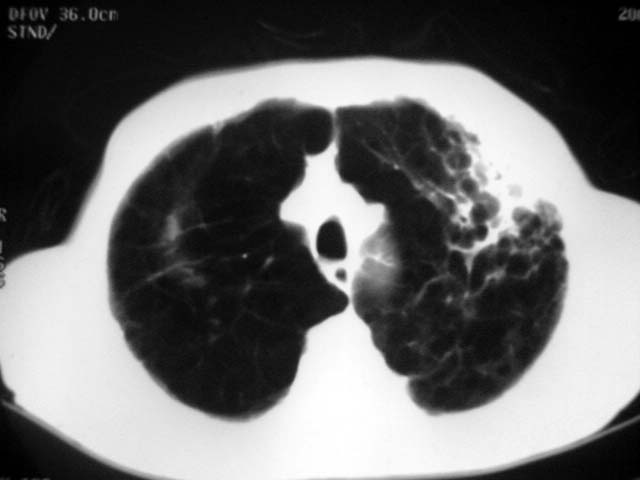

以下是引用zjzjr在2007-9-4 17:00:00的发言:[br]双上肺继发型结核伴左上肺空洞形成.慢性支气管炎伴肺气肿.